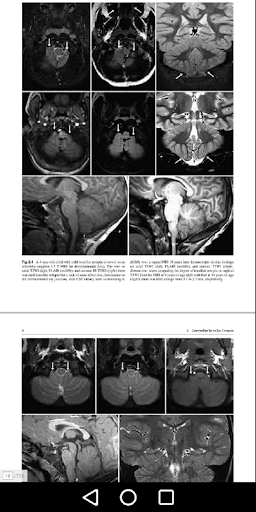

Cerebellar Tonsillar Ectopia

Cerebellar Flocculus Pseudomass

Mega Cisterna Magna dan Retrocerebellar Arachnoid Cysts